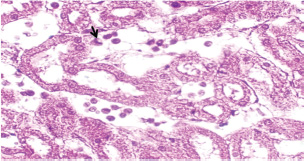

At 21 days post-infection, the lungs display moderate venous dilation and congestion, with abnormal leukocytes, indicating ongoing vascular compromise (Fig. 9). The liver showed necrotic changes in the fibrous capsule region, focal inflammatory cell infiltration, and intact hepatic cords, indicating sustained but localized damage (Fig. 10). The spleen exhibited plasma cell and macrophage proliferation within the red pulp, mild sinus dilation, and a few megakaryocytes, suggesting chronic immune activation (Fig. 11). The kidneys showed atrophic glomerular tufts and cystic dilation of adjacent tubules, indicating worsening renal pathology (Fig. 12). The mesenteric lymph nodes showed lymphoid follicles containing abnormal plasma cells and macrophages within the necrotic foci (Fig. 13).

Fig. 10. A histopathological section of liver of (G2) at 21 days postinfection showing necrotic finding in fibrous capsule region (black arrow) with focal inflammatory cell filtration with intact hepatic cords (H&E stain X 40).

Fig. 11. A histopathological section of the spleen (G2) at 21 days postinfection showing the main splenic findings characterized by proliferation of the plasma cell and macrophages within red pulp tissue with mild sinus dilation and few megakaryocytes (H&E stain X 40).